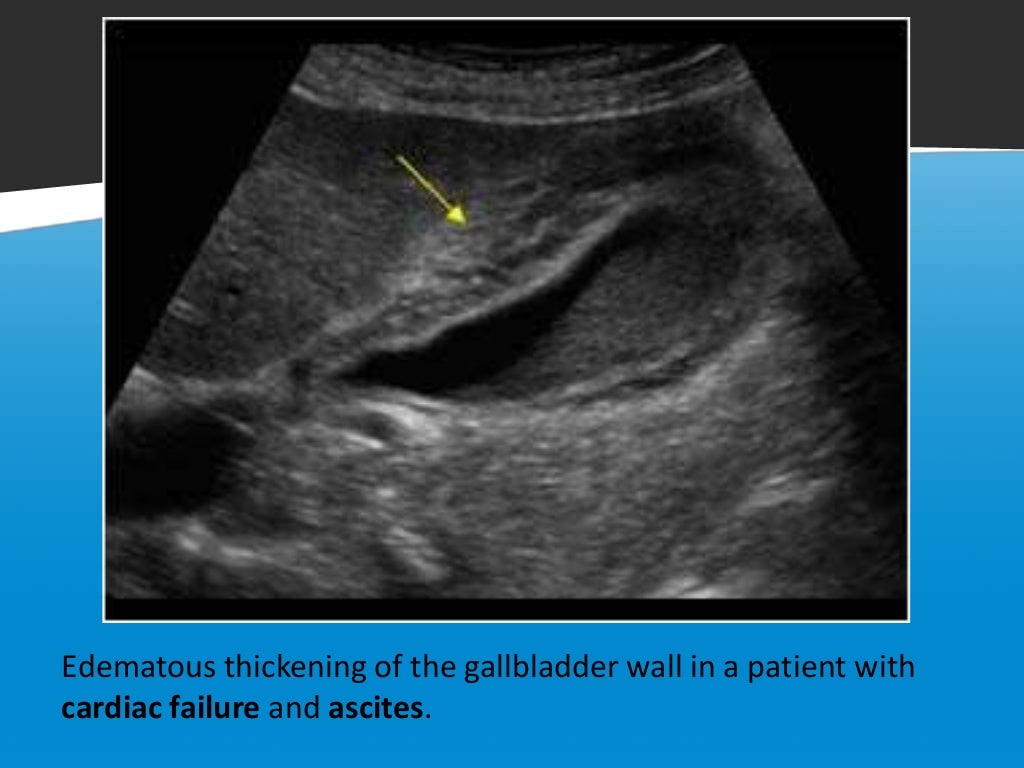

Diffuse Gallbladder Wall Thickening Differential Diagnosis AJR